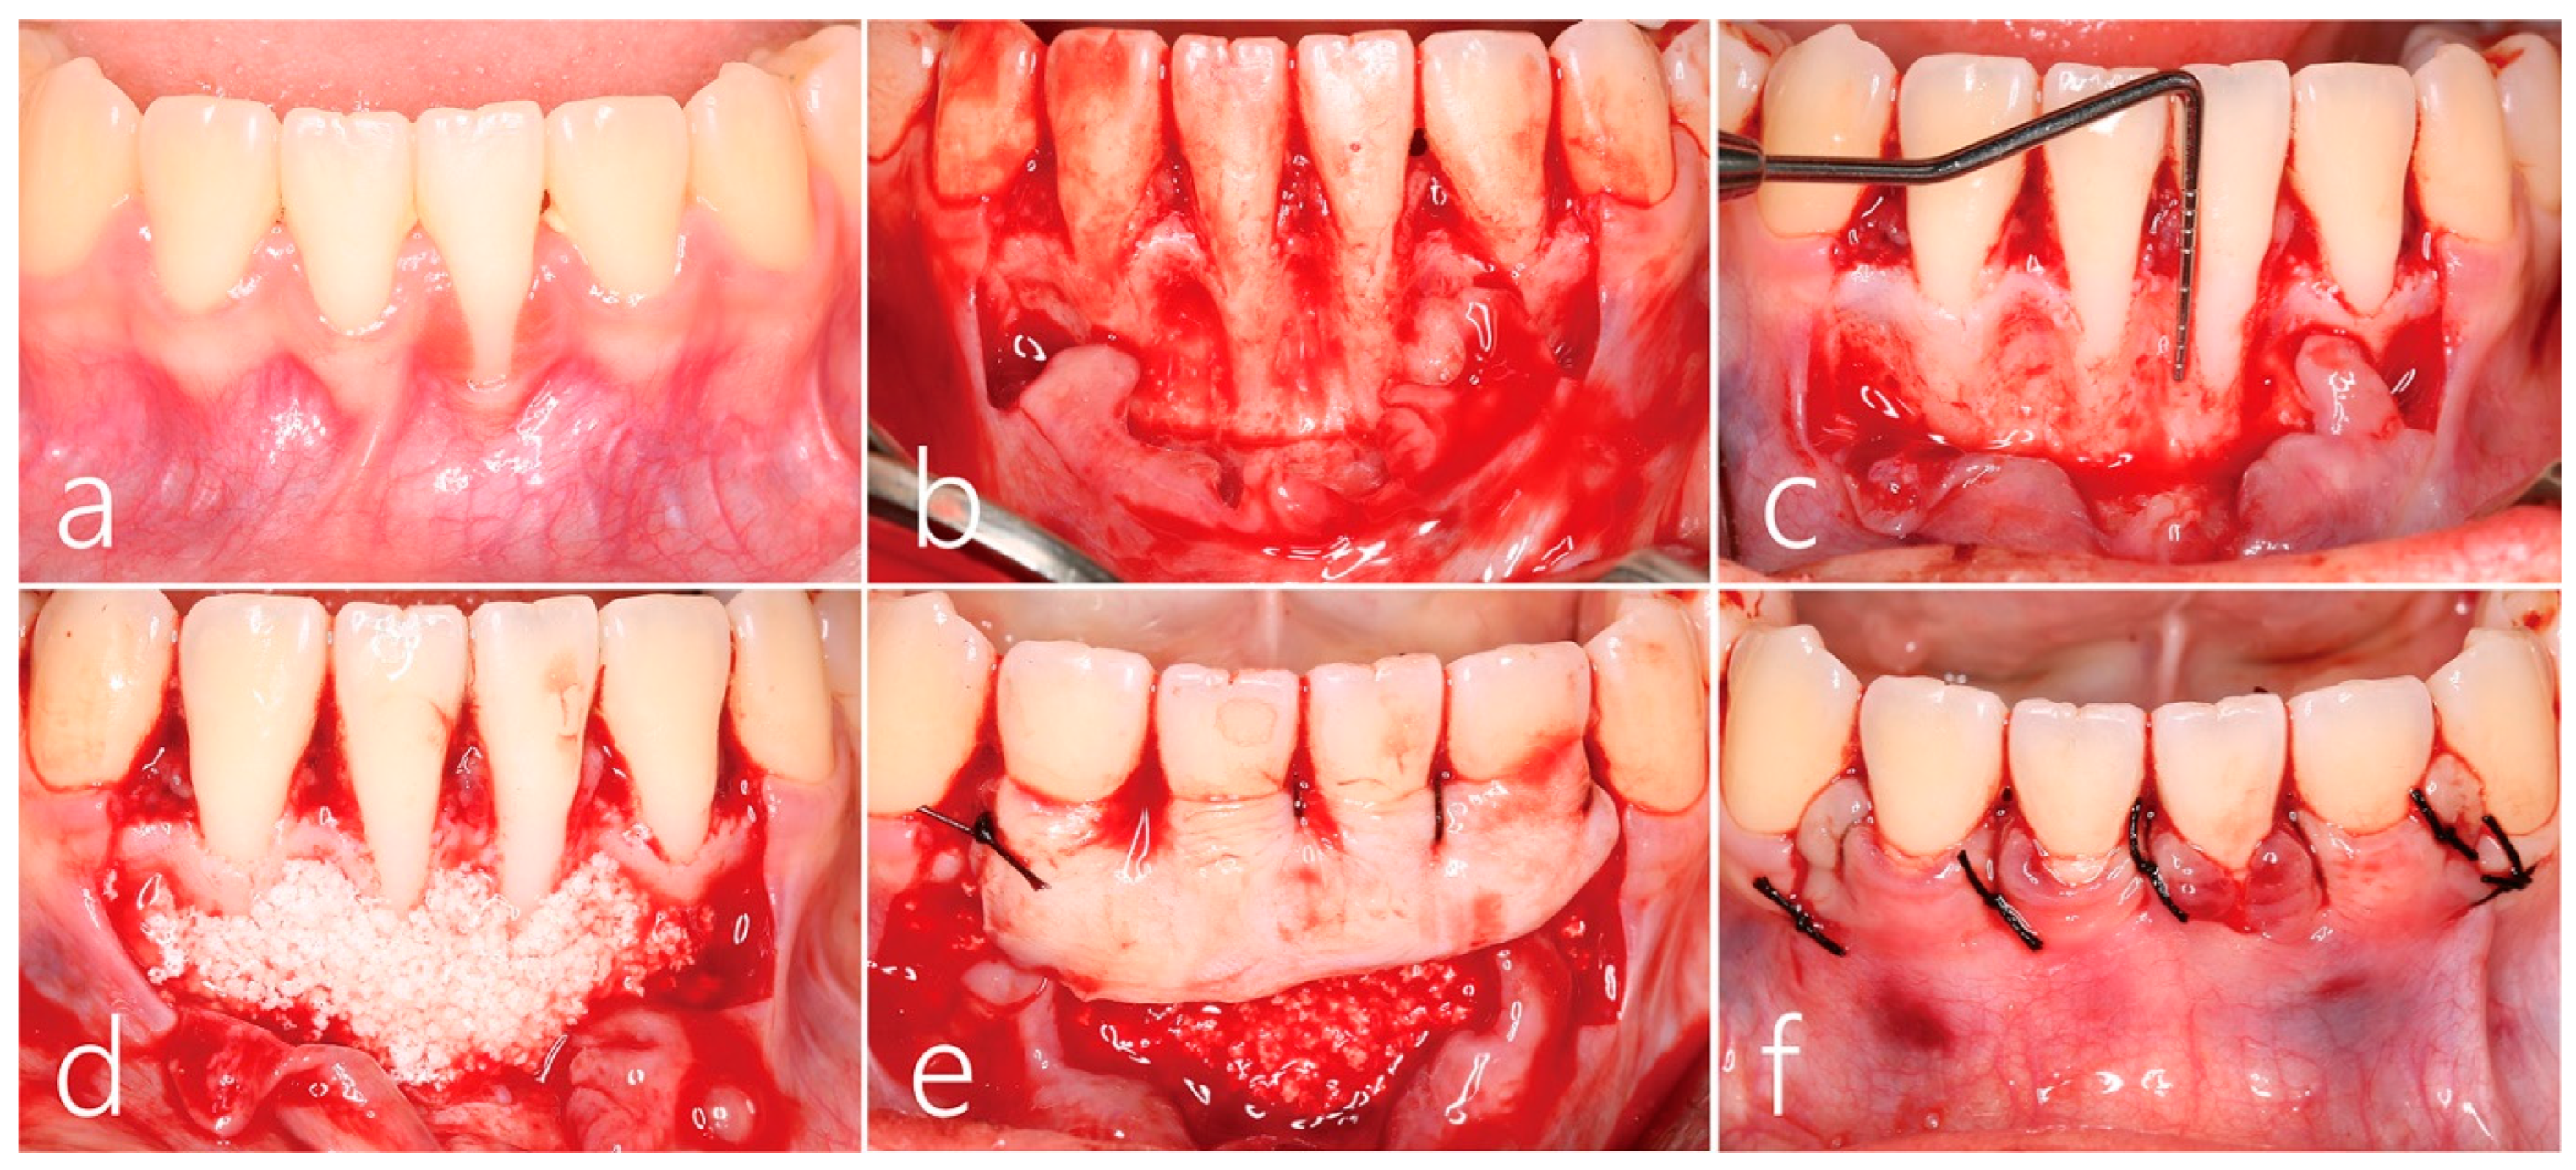

2. Case Report